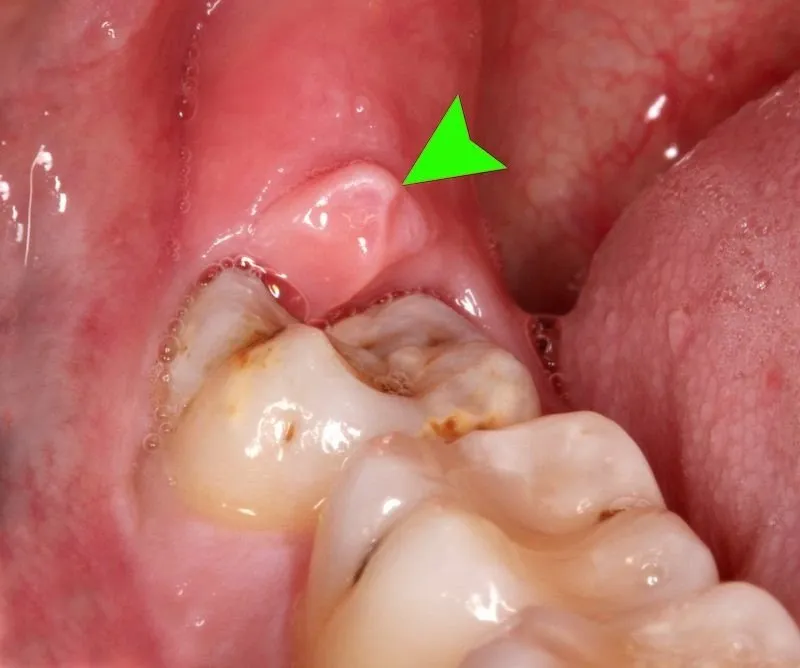

Hiện nay, cắt lợi là một trong những phương pháp điều trị viêm nhiễm và cải thiện thẩm mỹ. Với kỹ thuật cắt lợi hiện đại, điều